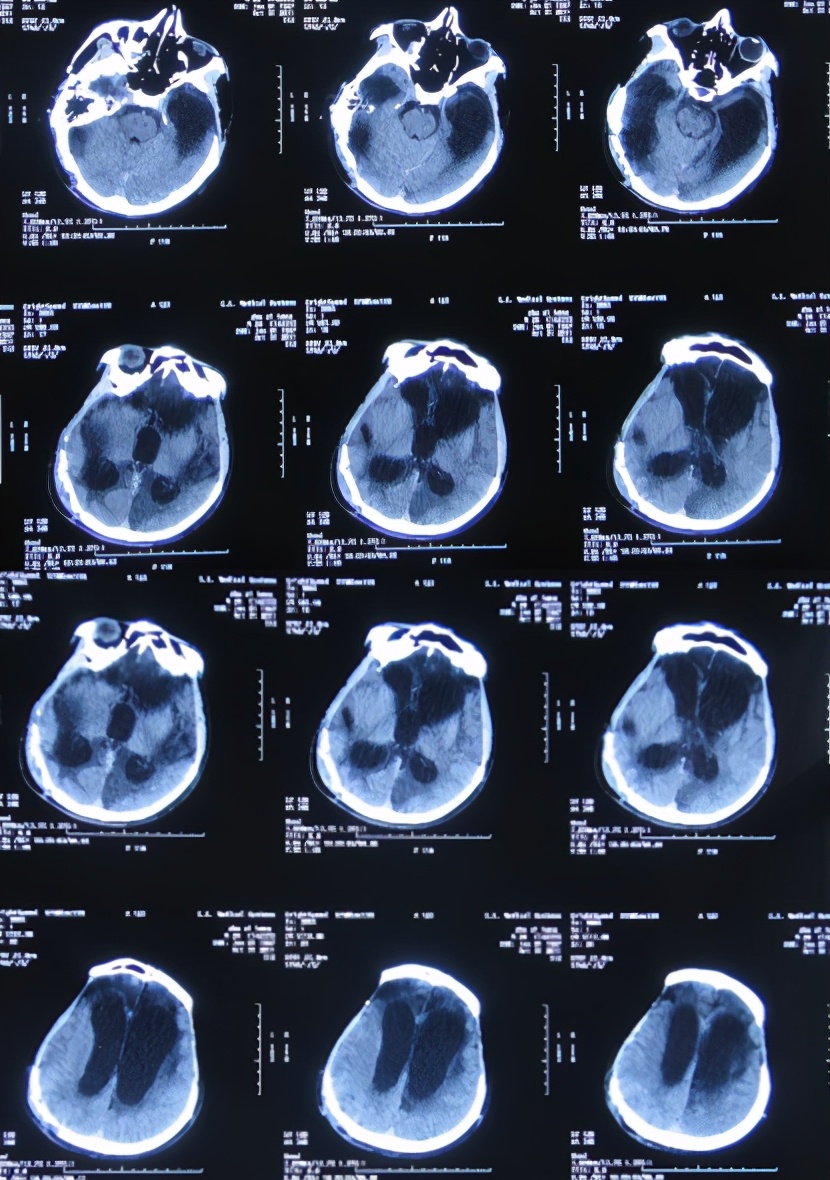

入院后3天即2011年11月10日,术前例行头颅CT( 图-10 )检查后,行侧脑室外引流术。

图-10: 2011年11月10日头颅CT

入院治疗21天即2011年11月28日,脑脊液颜色虽清亮,但仍有絮状物( 图-11 );头颅CT示脑积水有改善( 图-12 )。

图-12: 2011年11月28日头颅CT

入院治疗49天即2011年12月26日,例行复查头颅CT( 图-13 )后进行了左侧脑室-腹腔分流术。术后患者肢体较以前灵活,吃饭变正常。

图-13: 2011年12月26日头颅CT

入院治疗53天即2011年12月30日(脑室腹腔分流术后3天),患者肢体较入院时变灵活,吃饭也变正常,头颅CT示脑室缩小,骨窗变塌陷,但发现右侧原手术区有碎骨( 图-15 )。

图-15: 2011年12月30日头颅CT

入院治疗113天即2012年2月28日,查头颅CT示脑室进一步缩小( 图-17 )。

图-17: 2012年2月28日头颅CT

入院治疗127天即2012年3月13日(左侧颅骨修补术后6天),头颅CT示左侧颅骨修补术后,右侧仍有碎骨( 图-18 )。

图-18: 2012年3月13日头颅CT